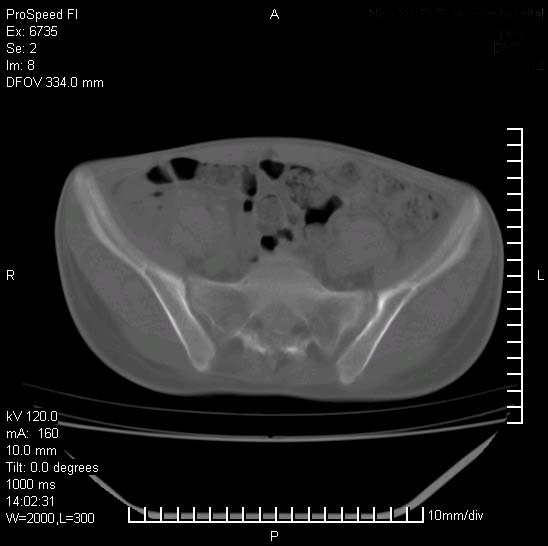

患者自诉胯部疼痛两年余,在当地服用中药,半月前至本院考虑骶髂关节结核,给予抗痨治疗。现发展至右下肢疼痛明显,活动受限,以膝关节处明显,拍膝关节平片无明显异常。

两侧骶骼关节改变,考虑强直性脊炎

左侧骶髂关节面限局性骨破坏,边缘硬化关节腔见钙化物;不出外tb

右侧骶髂关节也有类似改变,只是较左侧轻,首先考虑强直性脊柱炎,不除外结核,建议作hla-b27检查。

典型强脊炎改变,髋关节亦有累及

符合强直性脊柱炎表现。